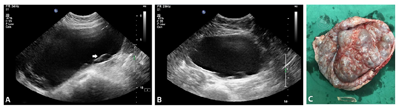

术后2年经腹超声发现右卵巢无回声区,大小4.8 cm×3.5 cm×3.5 cm,形态规则,边界清,内透声好。患儿雌孕激素水平正常,考虑不能排除生理性囊肿,随访观察半年,右附件区囊性包块逐渐增大至21.3 cm×18.1 cm×9.9 cm,形态规则,边界清,内透声好,其周边可见多发小卵泡样无回声结构,直径约0.5~1 cm(图2),CDFI:包块内未见明确血流信号。CT示腹盆腔内巨大囊性占位病变,增强扫描无强化。实验室检查:雌二醇171 pg/ml↑(27~122 pg/ml),孕酮、血LDH、NSE均正常。

行剖腹探查及右附件切除术,术中见右卵巢巨大单房囊肿,囊壁较厚,未见实性突起(图2)。病理示右卵巢幼年型颗粒细胞瘤,单囊型。